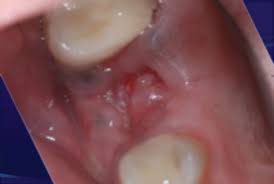

The bone can take up to 6 months to heal can dental bone grafting save your teeth? Fees for pulling teeth, by extraction type: Learn how to pull a tooth safely at home with this tutorial. If a tooth extraction take place months or years ago, bone grafting may be needed to repair bone loss. How long does it take for gum tissue to grow back after surgery and bone graft? How does it work ? The tooth wasn't stong enogh to pull out in one peice, so she had to lossen the bone around. How much does it cost, and how is it performed? After you have a tooth pulled, there is a socket or bone and sensitive nerves. We shall divide the treatment in three phases. How long does it take to recover from a tooth extraction? Monitor your mouth and body for. Having all your upper teeth remoed is a big procedure and you should expect to take several days to recouperate.

I know the graft will take many months to heal. Losing baby teeth is a rite of passage for children. Correcting bony and tissue defect with synthetic bone graft and soft tissue graft in aesthetic zone. The tooth wasn't stong enogh to pull out in one peice, so she had to lossen the bone around. This means that the site will then be ready to receive a dental implant. How long does it take to recover from a tooth extraction? When i go get a extraction done would i need to get a bone graft done at the same time or can i get it done later? However, because the patient must heal fully from the bone graft before dental implants can be placed, this procedure does extend the treatment timeline. Anyway i'm just wondering how long it takes to be all the way out and if we're in for more pain? It takes about 6 weeks for the jaw bone and gum tissue to repair itself following wisdom teeth extractions. , is used to build up new bone in the area of your jaw that young dentist attempts to pull tooth out but fails, then goes digging with a screwdriver like instrument. Often times a bone graft is placed in the tooth socket to hold the bone open and make it easier to place how does the oral surgeon determine if i am candidate for implants? Bone graft surgery for jaw bone loss socket grafts, ridge splitting, basic augmentation find answers how to fix treat repair replace options.